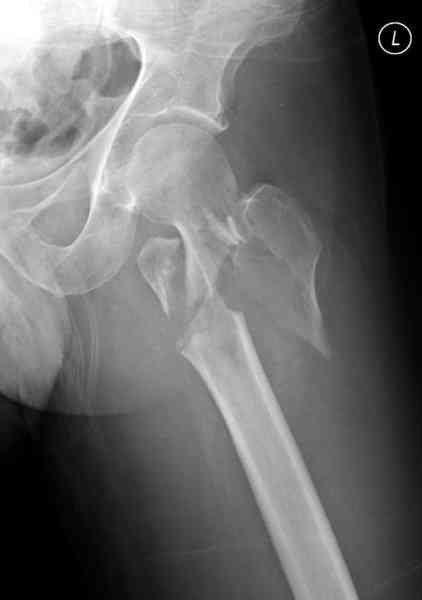

Re: [1/3] Перелом проксимального бедра

Алексей Семенистый 29 Апрель 2006, 15:13

Репозиция закрытая или минимально инвазивная насколько это возможно, с джойстиками поллерами и т.п. Остеосинтез PFN, PFNa, TFN, AFN, LFN,TGN... Полную нагрузку осрочить минимум на 2-3 месяца, далее смотреть по клинике и рентгенограммам...

При открытой репозиции вероятность анатомичной репозиции не велика, а вероятность получить аваскуляную кость - очень даже.